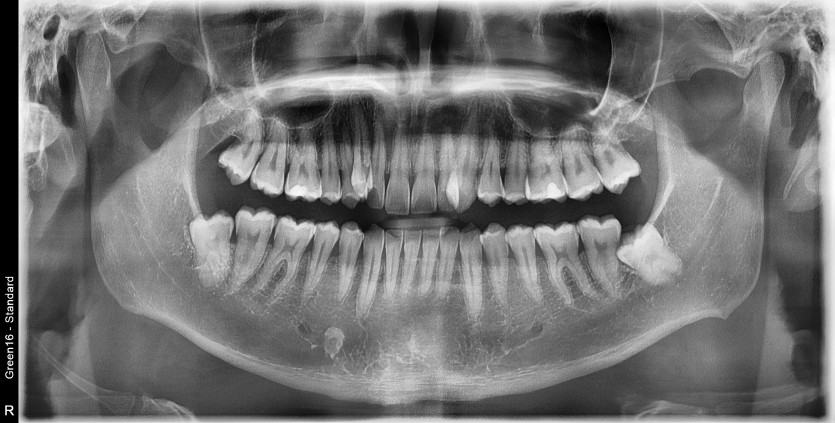

#18,28,38,48 사랑니 발치

구강 외과 전문의가 당일 발치했습니다.